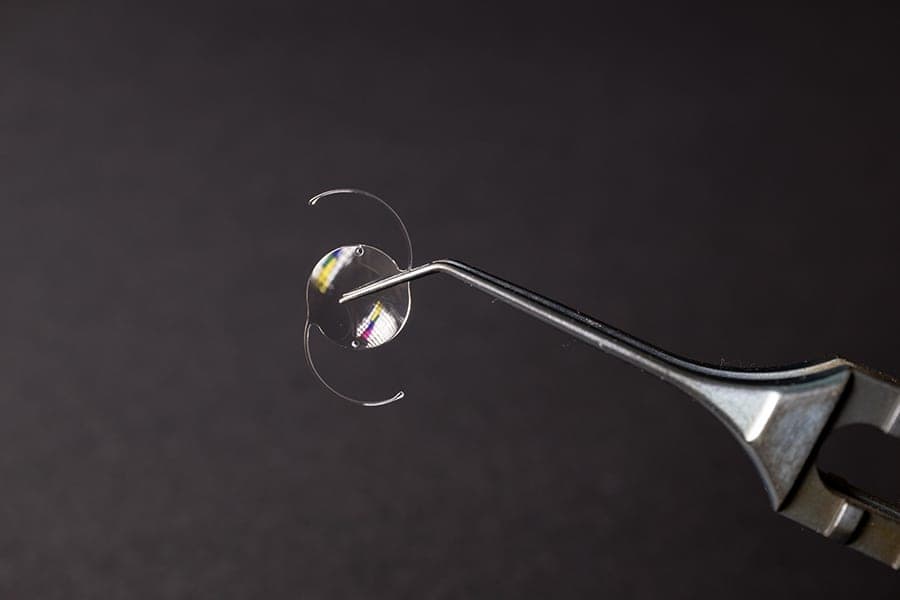

Lors d’une chirurgie de la cataracte, le cristallin opacifié est retiré puis remplacé par un implant artificiel. Transparent, il rétablit le passage normal de la lumière vers la rétine. Par ailleurs, selon leur type, les implants pour le traitement de la cataracte permettent de corriger d’autres troubles visuels associés : myopie, astigmatisme, presbytie ou hypermétropie.

Ainsi, le but premier du traitement chirurgical de la cataracte est de remplacer le cristallin opacifié du patient par un implant artificiel. Il est complètement transparent et permet donc de restaurer un cheminement normal des rayons lumineux à travers l’œil.

Cela étant dit, les implants pour le traitement de la cataracte ont une autre utilité : en fonction de leurs propriétés optiques, ils permettent de corriger les autres troubles visuels du patient, qu’il s’agisse de presbytie, d’astigmatisme, d’hypermétropie ou bien de myopie.

Les différents types d’implants pour le traitement de la cataracte

Les implants les plus simples sont dits « monofocaux ». Cela signifie qu’ils ne corrigent la vue du sujet qu’à une seule distance d’observation. Ainsi, le port de lunettes reste nécessaire dans certaines circonstances après l’opération.

Pour leur part, les implants multifocaux sont plus évolués. Ils permettent de corriger la vision du patient de près (généralement autour de 35 ou 40 cm), et de loin (au-delà de 1,5 à 2 mètres) lorsqu’il s’agit d’implants bifocaux. De plus, certains modèles « trifocaux » offrent également une bonne vision intermédiaire, par exemple pour le travail sur ordinateur.

Enfin, les implants « toriques » sont ceux utilisés pour les sujets astigmates. En effet, leur pouvoir de correction varie en fonction de l’axe de pénétration de la lumière dans l’œil, pour compenser le défaut de sphéricité cornéenne. Et, puisque l’astigmatisme s’accompagne souvent de myopie ou d’hypermétropie, il existe des implants toriques monofocaux, voire multifocaux, pour aussi prendre en charge ces défauts de vision.